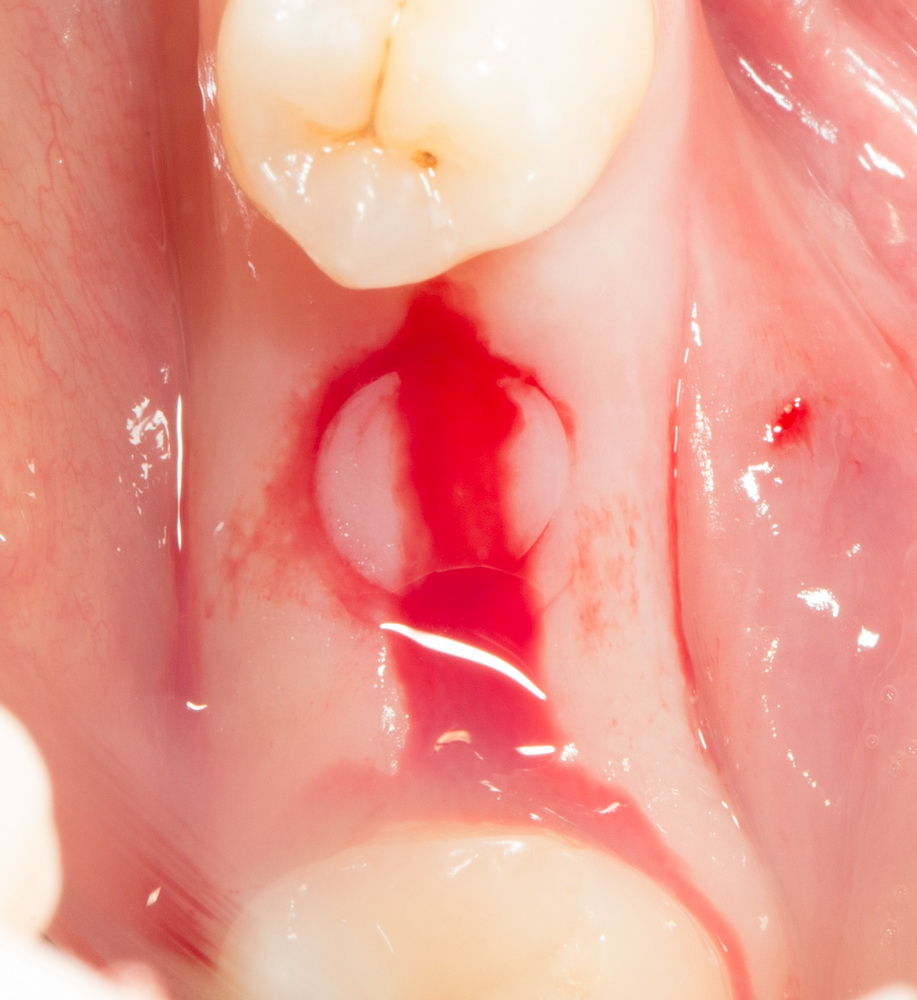

Можно поставить формирователь десны:

Операция закончена. Швы не нужны.

Вот картинка:

Можно аккуратно убрать формирователь десны и посмотреть, что там ниже:

Неплохо, правда? Осталось дождаться интеграции импланта (примерно 6 недель) — и можно приступать к протезированию.